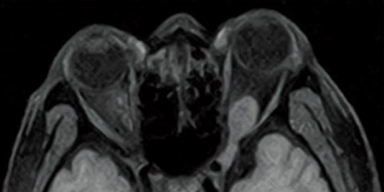

FSE-RADAR DWI

STIR

FatSep-T1WI

RADAR uses radial scan technology to mitigate motion artefact caused by a patient’s body movement due to voluntary or involuntary motion. Available with T2WI but also T1WI and FLAIR imaging in various plane and various body region including the head and shoulder joint, which are susceptible to respiration movements and the cervical spine that can be affected by swallowing movements. RADAR can help reduce repeat scans and improve image quality.